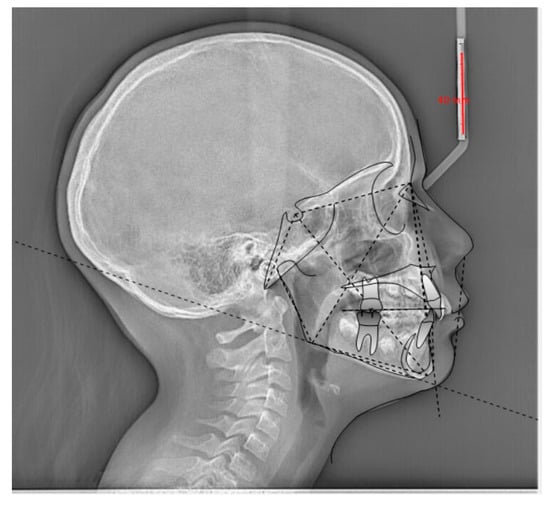

- Tsolakis, I.A.; Tsolakis, A.I.; Elshebiny, T.; Matthaios, S.; Palomo, J.M. Comparing a Fully Automated Cephalometric Tracing Method to a Manual Tracing Method for Orthodontic Diagnosis. J. Clin. Med. 2022, 11, 6854. [Google Scholar] [CrossRef] [PubMed]

| Ho Jin-Kim et al., 2022 [31] | Retrospective study | DCNN | A total of 1574 cephalometric pictures were included in the study. | The micro-average values of the DCNN-based AI model surpassed the automated tracing AI program in terms of performance. |

| Felix Kunz et al., 2020 [5] | Retrospective study | A customized open-source CNN DL algorithm (Keras and Google TensorFlow) is directed toward analyzing visual imagery and has an input layer, multiple hidden layers, and an output layer. | Both AI and each examiner analyzed 12 orthodontic parameters based on cephalometric images. | No clinically relevant difference was noticed between the two analyses. |

| Jaerong Kim et al., 2021 [40] | Retrospective study | A cascade network consisting of ROI detection and landmark prediction. | Two orthodontists evaluated 100 lateral cephalograms and the mean of these values was considered the gold standard. The DL model evaluated 3150 lateral cephalograms. | The overall automated detection error was 1.36 ± 0.98. The accuracy of CL recognition was comparable with that made by two orthodontists with more than 10 years of clinical experience. |

| Sangmin Jeon et al., 2021 [41] | Retrospective study | CephX for the AI analysis. | The cephalograms were analyzed with V-ceph for the conventional CA and with CephX for the AI analysis. | Variations were found in saddle angle, linear measurements of maxillary incisor to NA line, and mandibular incisor to NB line. |

| Mehmet Uğurlu et al., 2022 [42] | Retrospective study | AI system (CranioCatch, Eskisehir, Turkey). | A CNN-based AI algorithm for automatic CL detection was developed and used to detect CLs.Then, an orthodontist with 9 years of experience analyzed the CA of the AI. | There were no statistical differences between manual identification and AI groups in 11 out of 16 points. AI increased the efficiency of CL identification. |

| Gökhan Çoban et al., 2022 [43] | Retrospective study | WebCeph was used for AI-based CA. | Differences between using the semi-automated software Dolphin® (v. 11.5, Chatsworth, CA, USA) and WebCeph (WEBCEPH™, Artificial Intelligence Orthodontic & Orthognathic Cloud Platform, South Korea, 2020) software for each CL. | It was determined that there was a noticeable change between SNB, ANB, and SN.PP, U1.SN, U1-NA, U1.NA, L1-APog, IMPA, L1-NB, and ULE. |

| Ioannis A Tsolakis et al. [44] | Retrospective study | CS imaging V8 software was used for AI-based CA. | The difference between using semi-automated software Dolphin® 3D Imaging program (version 11.0) and CS imaging V8 software for each CL. | There were no significant differences between the two methods (p > 0.0027) for the SN-MP, U1-SN, SNA, SNB, ANB, L1-NB, SNPg, ANPg, SN/ANS-PNS, SN/GoGn, U1/ANS-PNS, L1-APg, U1-NA, and L1-GoGn landmarks. |